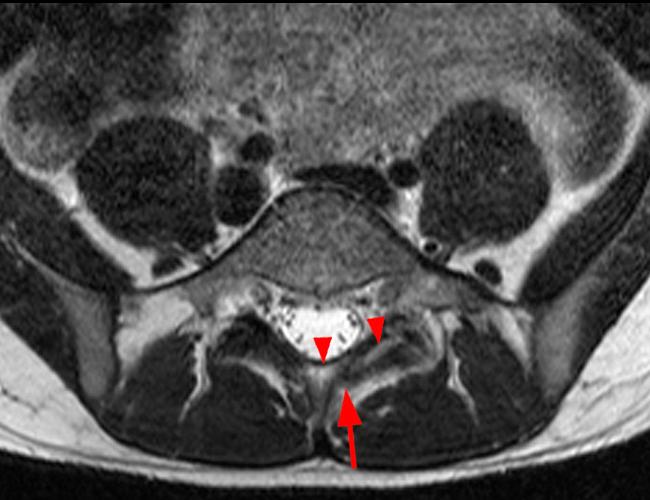

Case 2: T1-weighted (4A) and T2-weighted (4B) axial images show T1 hypointensity and T2 hyperintensity (arrowheads) in the left lamina of L5 adjacent to a small hypointense line (arrows) which traverses the lamina.

Case 2: Acute left-sided laminolysis